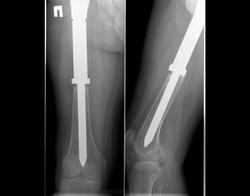

Все снимки сделаны через 10-30 лет после эндопротезирования

Снимки 4,5,6 пациентки, которой была сделана резекция бедренной кости с эндопротезированием коленного сустава 30 лет назад по поводу остеосаркомы. Расшатывание эндопротеза клинически стало себя проявлять 5 лет назад (снимок 4), далее довольно быстро прогрессировало, что по-видимому усугубилось присоединившимся остеомиелитом (снимки 5, 6 - теперешние). Пришлось выполнить ампутацию, тем не менее, человеку дали 25 лет нормальной, полноценной жизни.